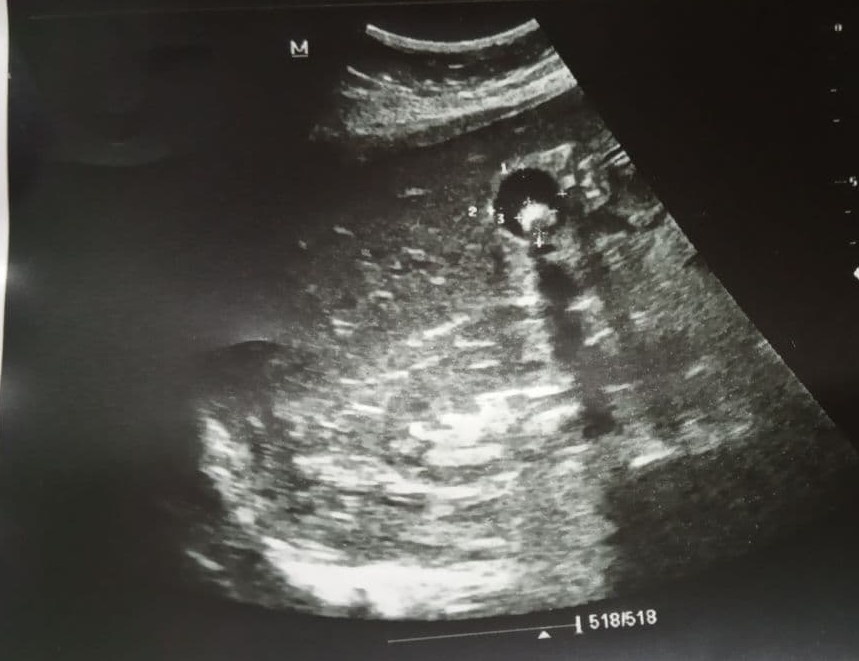

Желчнокаменная болезнь (развитие и прогрессирование) в XX веке признана медленной эпидемией. В XXI веке мы также наблюдаем увеличение частоты данного заболевания. Пациенты в Областных центрах и в отдалённых населённых пунктах нуждаются в специализированной медицинской помощи. Современные технологии стремительно развиваются. Необходим комплексный подход к лечению желчнокаменной болезни и её осложнений. Приведу клинический пример. Поступает пациентка 47 лет с признаками механической желтухи. При ультрасонографии (УЗИ) желчного пузыря диагностирован крупный конкремент с акустической тенью и изменением своего положения при движении пациентки.

Дополнительно выполнен осмотр Большого дуоденального сосочка (Фатерова сосочка).

Диагностирован холедохолитиаз.